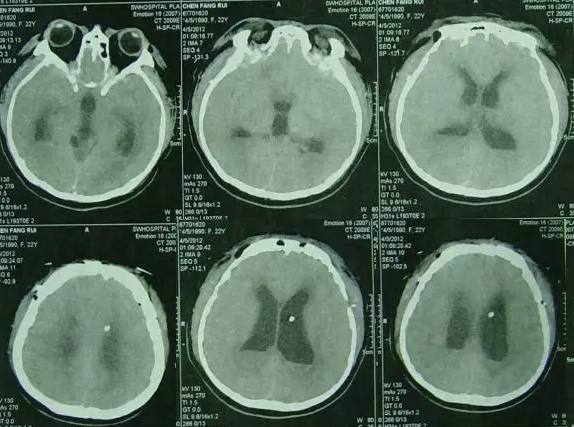

内镜造瘘术后当天再次开颅进行了硬膜下血肿清除术,并留置右侧侧脑室外引流管,术后患者意识变清,查头颅CT:血肿基本消失(图-2)。

图-2:2012年4月28日开颅术后头CT

内镜造瘘术后第2天即2012年4月30日,行头颅CT:“三脑室内缩小”(图-3),进行腰穿检查颅内压为170mmH20,随拔除脑室外引流管。

图-3:2012年4月30日头CT